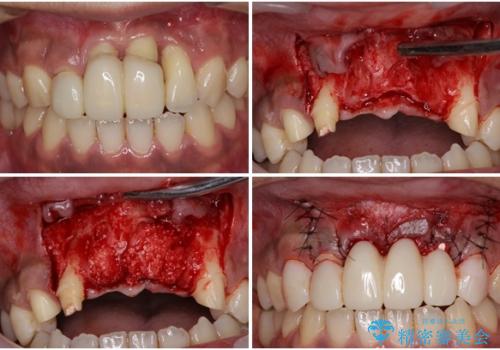

- ソーシャルメディアでのゲームに夢中になっている最中に車と接触し、前歯の抜歯を余儀なくされた患者様です。

初診時では前歯が保存できる可能性も模索しましたが、損傷が激しく3歯を抜去することとなりました。

保存となった隣在歯も神経が失活していており、補綴治療が必要であったので、オールセラミッククラウンにて補綴治療することとしました。

スマートフォンに集中するがあまり周囲への注意を欠き、信号無視などによる接触事故は増えているようです。

歯をぶつけた代償は大変大きなものとなりますので、注意が必要です。